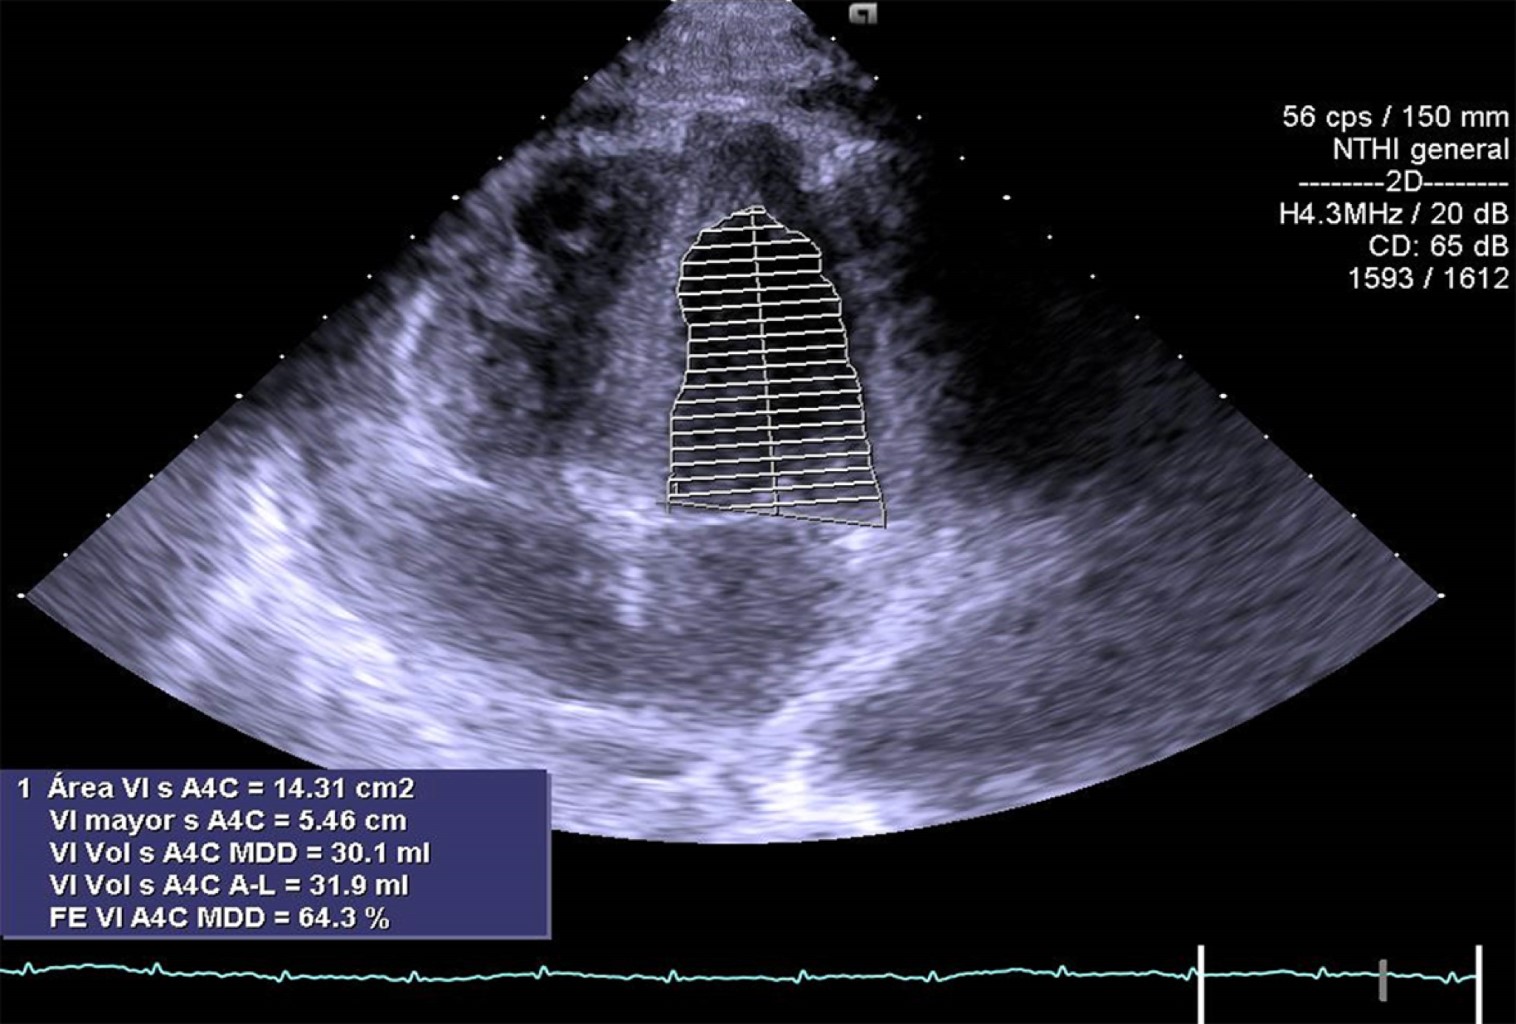

Mujer de 17 años de edad sin antecedentes de importancia, la cual ingresa al área de urgencias trasladada por paramédicos en camilla después de sufrir trauma debido a desaceleración súbita por caída de 10 metros de altura, sufriendo contusión directa y múltiples fracturas en miembros pélvicos, pelvis y cara, por lo que se le realizó colocación de fijadores externos en pelvis y lavado quirúrgico. Ingresó a terapia intensiva con Glasgow de 15 puntos, facies álgica, palidez de piel y tegumentos, con dolor intenso en pelvis escala visual analógica (EVA) 9/10. Con requerimiento de oxígeno suplementario a cinco litros por minuto con disminución de los movimientos de amplexión y amplexación del hemitórax derecho, matidez a la percusión, aumento de las vibraciones vocales y disminución de murmullo vesicular en región basal de hemitórax derecho; signos vitales: presión arterial (TA) 90/50 mmHg, frecuencia cardiaca (FC) 109 latidos por minuto (lpm), frecuencia respiratoria (FR) 16 respiraciones por minuto (rpm), saturación periférica de oxígeno (SpO2) 100%, temperatura 36.6°C, llenado capilar 4 s. Laboratorio: hemoglobina (Hb) 6.8 g/dL, hematocrito (Hct) 19.9%, plaquetas 88,000 × 109/L, tiempo de protrombina (TP) 17.3 s, tiempo parcial de tromboplastina (TPT) 27.5 s, índice internacional normalizado (INR) 1.29, creatina fosfocinasa (CPK) 1,282.52 U/L, isoenzima MB de la creatina cinasa (CPK-MB) 1.2 ng/dL. Se realiza tomografía de abdomen, la cual evidencia hematoma retroperitoneal evolutivo desde plano fascial y perirrenal posterior. La paciente ameritó ventilación mecánica y fue sometida a laparotomía exploradora de urgencia. A su egreso de quirófano y posterior a la reanimación con hemoderivados, continuó con datos de choque con TA 60/40 mmHg, frecuencia cardiaca 105 lpm, llenado capilar 5 s, por lo cual requirió manejo con doble vasopresor: norepinefrina 0.15 μg/kg/min y vasopresina 0.03 UI/h; sin embargo, continua con presión arterial media < 65 mmHg. Se le realiza radiografía de tórax (Figura 1) donde se observa contusión pulmonar en región basal de hemitórax derecho, con corazón en gota. Electrocardiograma (ECG) (Figura 2): ritmo sinusal, frecuencia cardiaca 120 lpm, con aplanamiento de la onda T en la mayoría de las derivaciones excepto en V2, depresión del segmento ST en aVR y ausencia de elevación del segmento ST en V1. Se realizó ecocardiograma transtorácico (ECOTT) (Figuras 3 y 4), en el que se observa movilidad conservada solamente en ápex, condicionando tracción del ventrículo derecho; resto con hipocinesia generalizada, ventrículo derecho dilatado con función sistólica global deprimida con hipocinesia generalizada, fracción de eyección del ventrículo izquierdo (FEVI) 21.7%, puntaje InterTAK de 49 puntos. Requirió manejo con inotrópico dobutamina 3 μg/kg/min con mejoría de presión arterial media y datos de choque. Presentó una evolución favorable, logrando retiro de inotrópico 24 horas después por mejoría con control ecocardiográfico seis días después (Figura 5), con recuperación de FEVI: 64.3%. La paciente requirió fijación de fracturas de huesos de la cara y miembros pélvicos y posteriormente fue trasladada a otra unidad hospitalaria para continuar con tratamiento ortopédico.

Figura 3